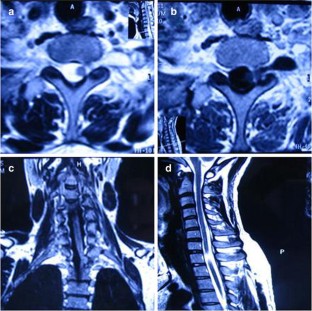

Fig. 1